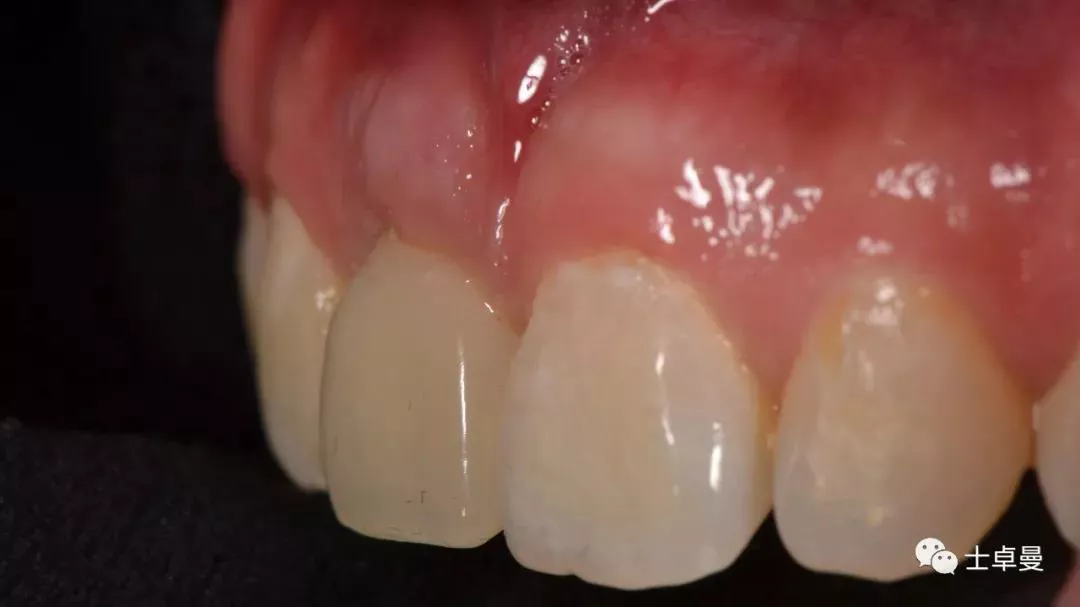

临时修复后2个月,龈缘及龈乳头位置理想,软组织健康

· 2个月后,见唇侧骨弓轮廓可,龈缘及龈乳头形态自然,去11临时修复体,植体ISQ值测定82,个性化取模,试戴Variobase氧化锆基台+LAVA氧化锆单冠,就位被动性良好,增加基台扭力至35Ncm,粘接固位上部冠,调合抛光。